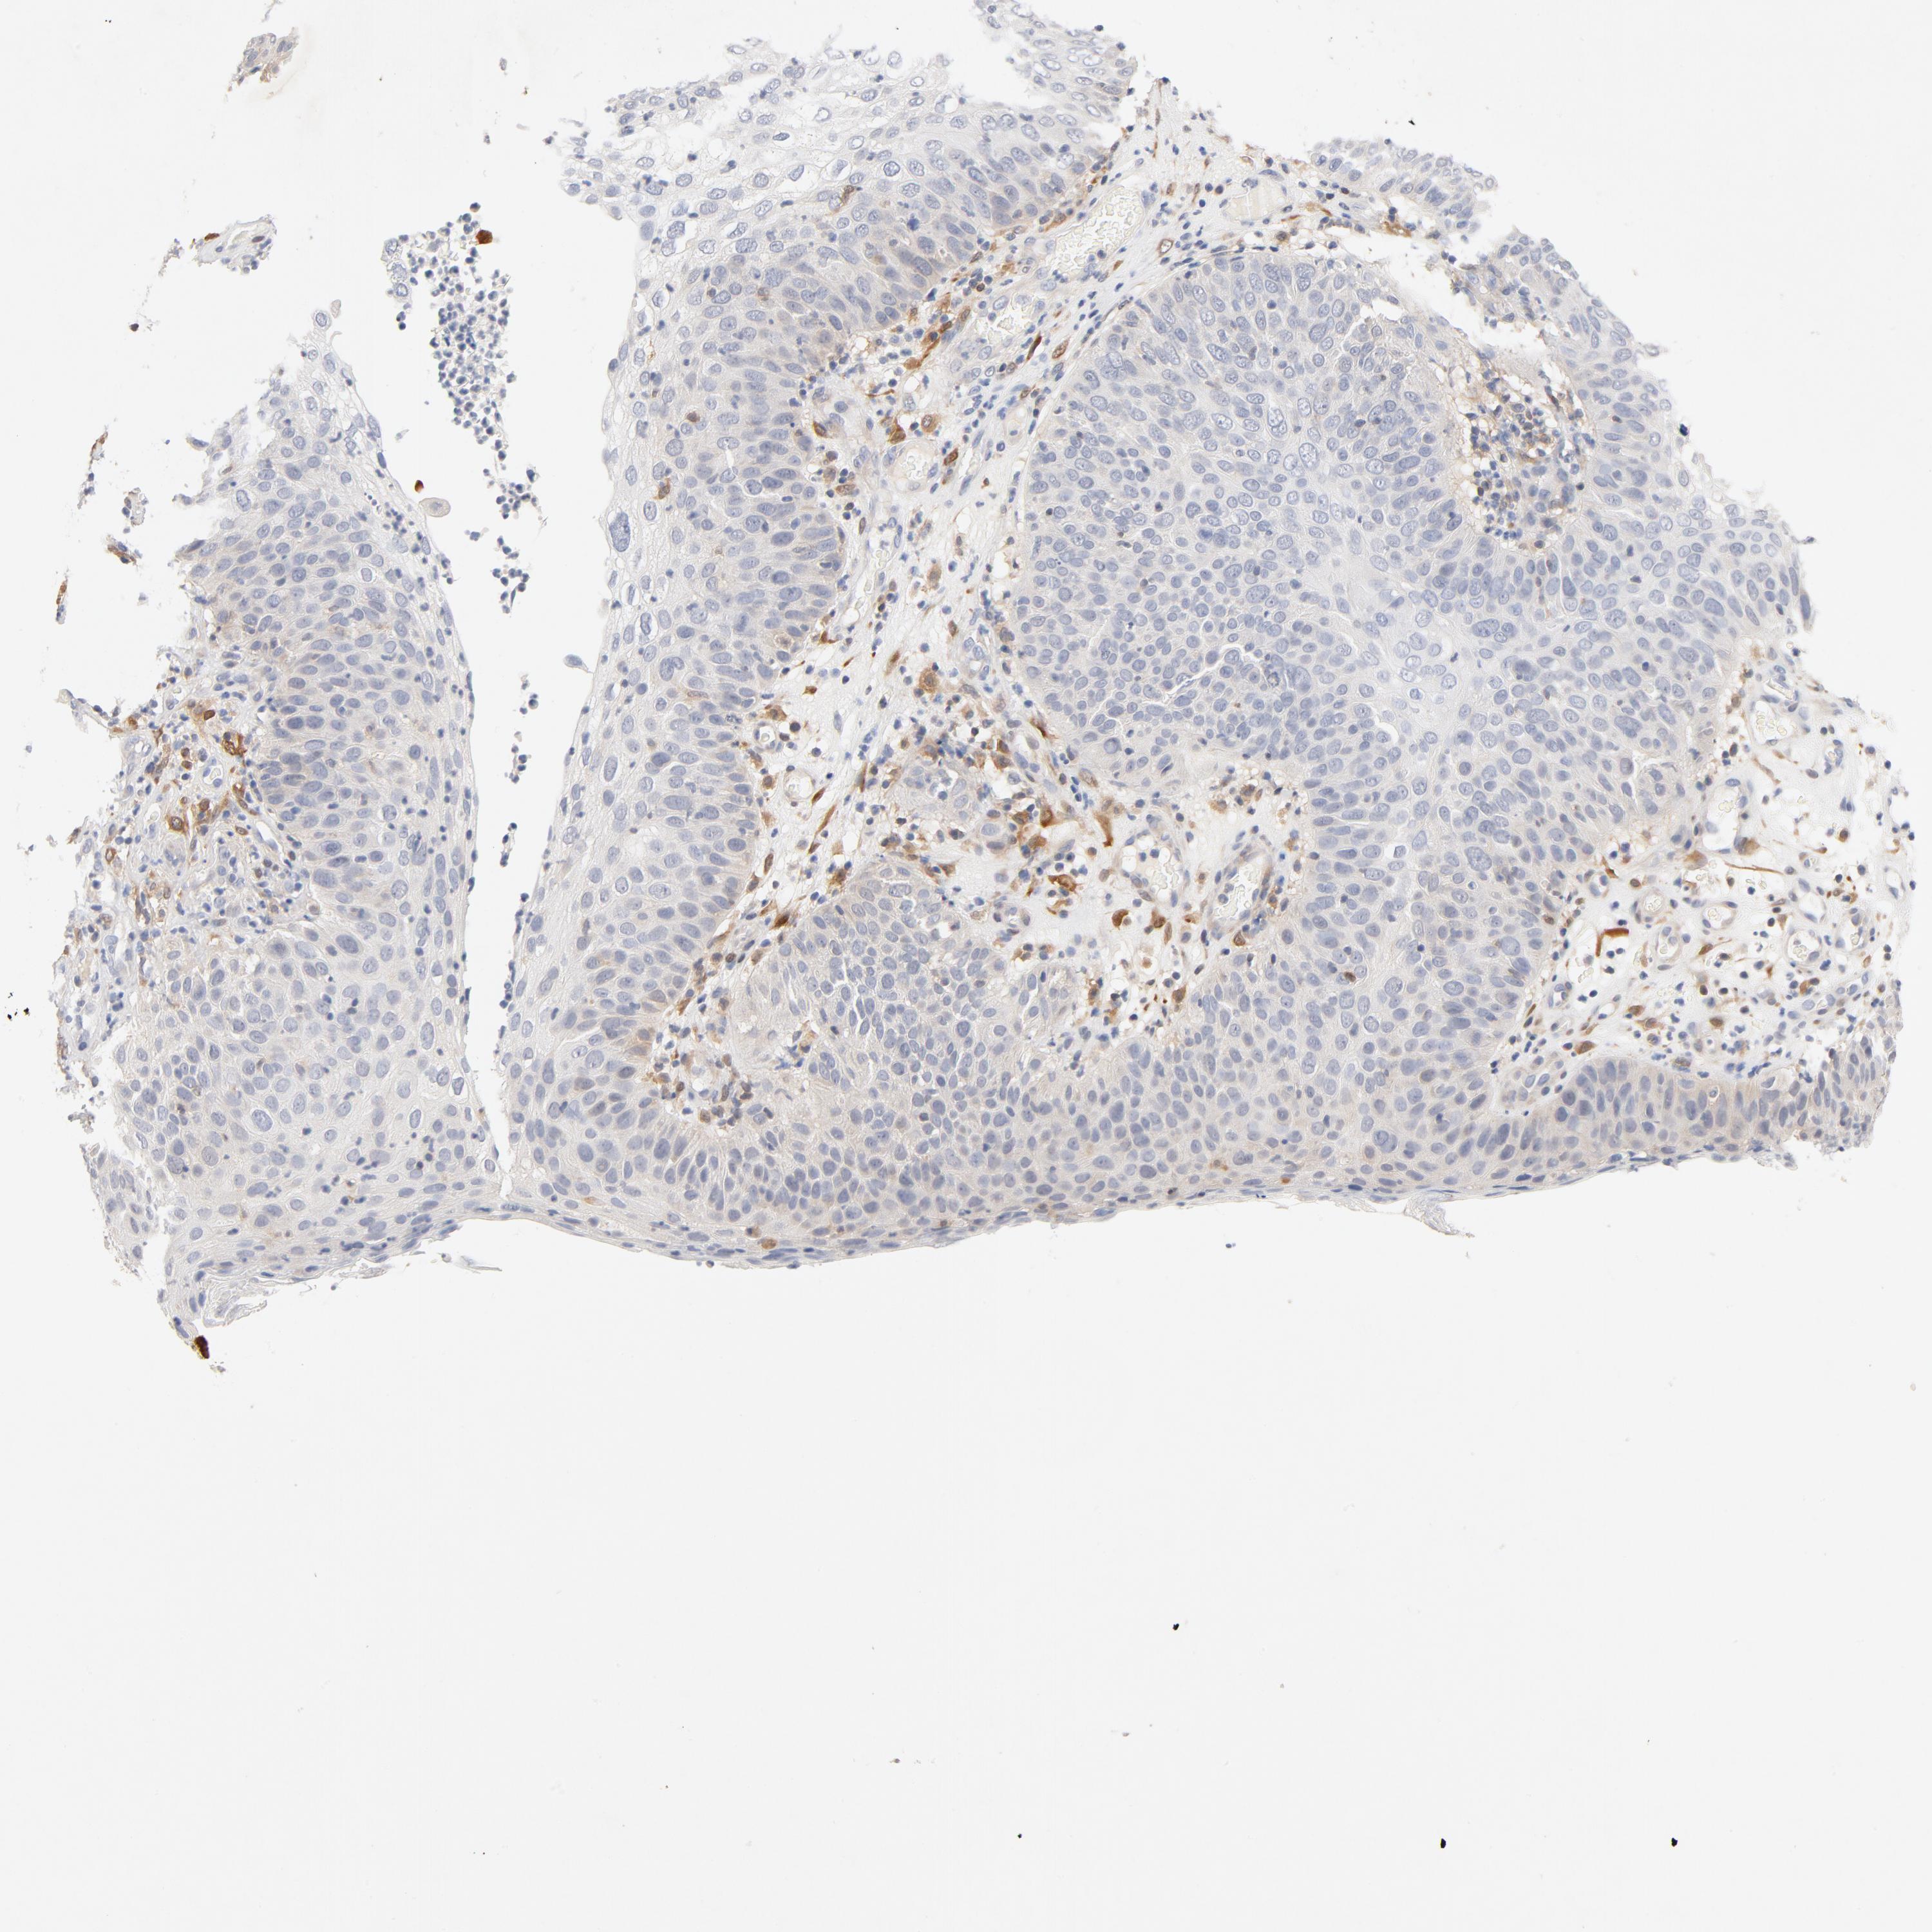

CANCER SKIN CANCER Show tissue menu

SKIN CANCER - Protein expressioni

A mouse-over function shows sample information and annotation data. Click on an image to view it in a full screen mode. Samples can be filtered based on level of antibody staining by selecting one or several of the following categories: high, medium, low and not detected. The assay and annotation is described here.

Each image is clickable and will lead to virtual microscopy that enables deeper exploration of all samples and also displays staining intensity scores, fraction scores and subcellular localization as well as patient and tissue information for each sample.

Antibody HPA000931

Antibody HPA000982

Antibody CAB004049

Staining

High

Medium

Low

Not detected

Intensity

Strong

Moderate

Weak

Negative

Quantity

>75%

75%-25%

<25%

None

Location

Nuclear

Cytoplasmic/membranous

Cytoplasmic/membranous,nuclear

Squamous cell carcinoma, NOS

Basal cell carcinoma